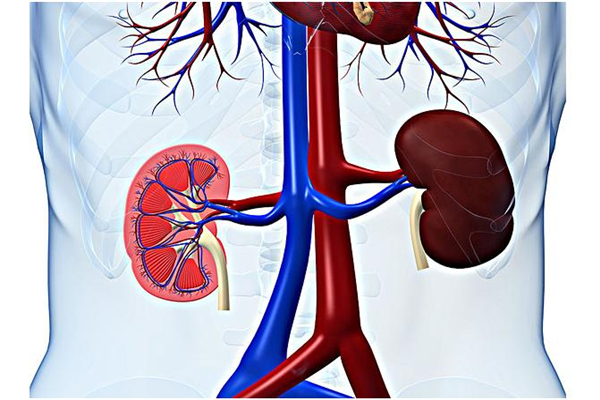

腎臟